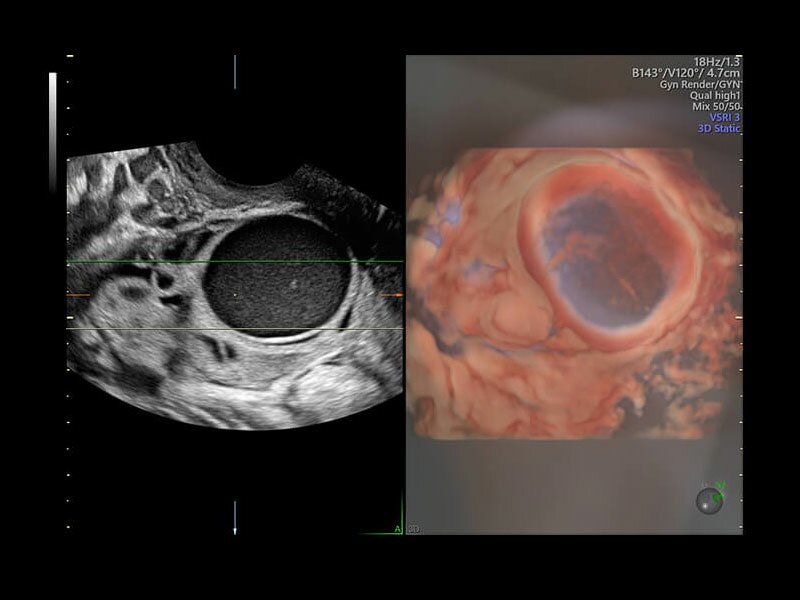

• Программа 3D и режим инверсии (при наличии специализированных датчиков)

• Advanced VCI (Volume Contrast Imaging) - расширенный программный пакет объемного контрастного изображения (VCI) для механических и электронных объемных датчиков:

• Проведение любой произвольной плоскости в 3D/4D (OmniView)

• Объемное контрастирование любой произвольной плоскости (OmniView+VCI)

• VOLUME CALCULATION II (VOCAL, Virtual Organ Computer Aided Analysis) – программное обеспечение для полуавтоматического определения контуров структур и расчета их объема в режиме объемной реконструкции для механических и электронных объемных датчиков

• SonoAVC (Sonography based Automated volume Count аnalysis) - программа для автоматического расчета размеров и объема анэхогенных образований/структур в режиме объемной реконструкции. Включает программу для расчета фолликулов и программу для расчета других анэхогенных структур для механических и электронных объемных датчиков

• Усовершенствованный режим объемной визуализации с контрастированием (Volume Contrast Imaging, VCI) и опция OmniView

• Повышает контрастное разрешение и улучшает визуализацию области интереса в любой плоскости сечения, даже при исследовании структур неправильной формы.

• SonoAVC (Sonography-based Automated Volume Count) — инновационный инструмент для визуализации и измерения гипоэхогенных структур, в том числе фолликулярного аппарата и мозга плода, а также для выполнения соногистерографии.